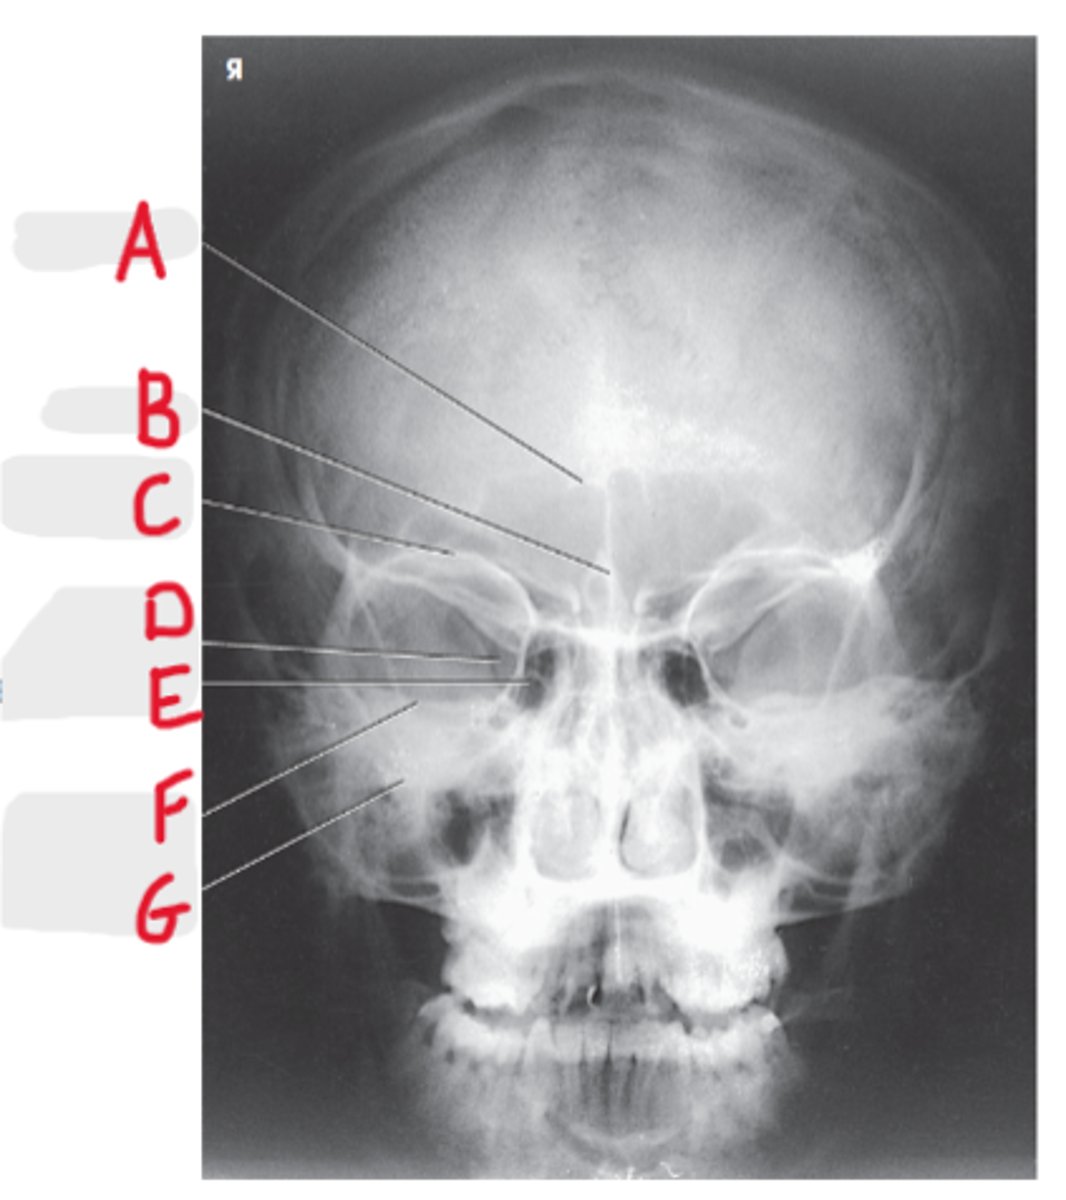

Frontal sinus

A

Crista galli

B

Superior orbital margin

C

Superior orbital fissure

D

Ethmoid sinus

E

Petrous ridge

F